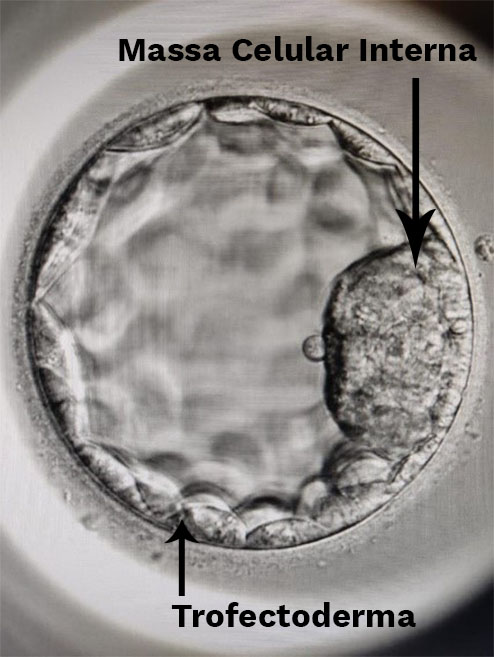

Para se realizar o PGT, é necessário inicialmente fazer uma biópsia do embrião. A biópsia embrionária é realizada na fase de blastocisto, ou seja, no quinto dia após a fecundação (120 horas), o que permite avaliar um número maior de células (de 6 a 10) e, consequentemente, obter um resultado mais preciso. O procedimento consiste na retirada de células do trofectoderma do embrião, ou seja, a região externa formada por células que vão originar as estruturas da placenta e membranas.

A retirada das células embrionárias ocorre após a realização de uma pequena abertura na região externa do blastocisto. Algumas células que se exteriorizam por essa abertura são delicadamente aspiradas e encaminhadas ao laboratório de genética. É muito importante que a biópsia seja realizada de maneira correta para que não comprometa o desenvolvimento do embrião no futuro. Ressaltamos que a biópsia não afeta massa celular interna, ou seja, porção do blastocisto que originará o feto propriamente dito, não prejudicando o futuro bebê.